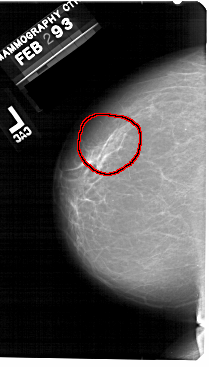

A_1493_1.LEFT_MLO

FILE: A_1493_1.LEFT_MLO.OVERLAY

TOTAL_ABNORMALITIES 1

ABNORMALITY 1

LESION_TYPE CALCIFICATION TYPE PLEOMORPHIC DISTRIBUTION SEGMENTAL

ASSESSMENT 4

SUBTLETY 4

PATHOLOGY BENIGN

TOTAL_OUTLINES 1

BOUNDARY